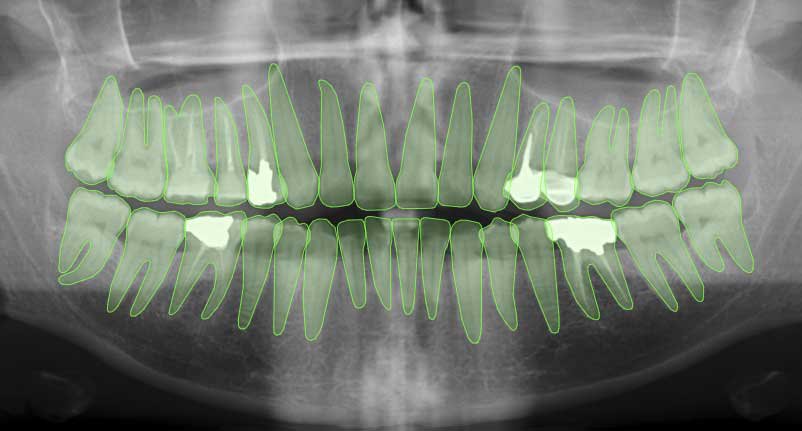

Semantic segmentation of a dental X Ray image

Semantic segmentation is widely used across various industries:

- Medical Imaging: Detecting and labeling organs, tissues, or abnormalities in MRI or dental scans to support diagnosis.